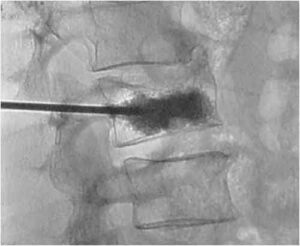

Presso l’Unità Operativa di Neurochirurgia dell’’Ospedale Santa Chiara di Trento, diretta dal Dottor Franco Chioffi, vengono operati circa 700 pazienti...